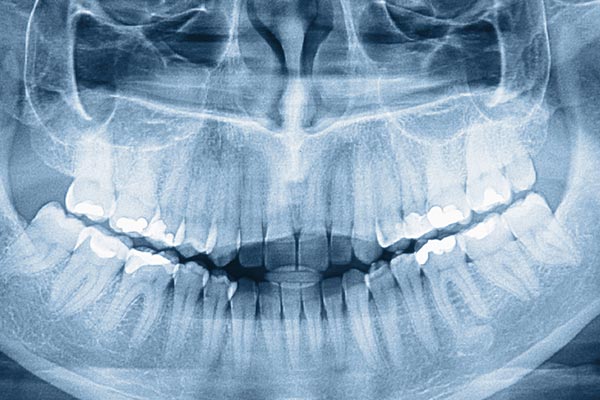

Modern orthodontic care begins with seeing the problem clearly. High-resolution digital imaging replaces traditional film with sensitive electronic detectors that capture fine detail in a fraction of the time. These images appear on-screen almost instantly, allowing your clinician to evaluate tooth positions, root alignment, and jaw relationships during the same appointment rather than waiting for film to develop. Faster imaging means quicker decisions and a more informed conversation about treatment options.

Because digital images are captured and stored electronically, they can be enhanced and reviewed from multiple angles without degrading the original data. Adjustments such as contrast enhancement and zooming help reveal subtle features that support accurate diagnosis and efficient treatment planning. Digital imaging also supports multiple views at once, so the dentist and patient can look at the same image together and discuss findings in real time.

We use high-resolution digital radiography and advanced sensor technology to capture clear images of tooth roots, jaw relationships and overall oral anatomy. These images appear on-screen almost instantly, allowing clinicians to evaluate findings during the same appointment and discuss options with patients in real time. Digital imaging often includes panoramic or cephalometric views when needed to assess growth, alignment and skeletal relationships.

Digital images can be enhanced and reviewed from multiple angles without degrading the original data, which supports more accurate diagnosis and treatment planning. The immediate availability of images reduces the need for repeat exposures and helps the care team design predictable, individualized treatment sequences. At Longo Dietz Orthodontics we pair high-quality sensors with streamlined workflows so every diagnostic image directly informs excellent patient care.